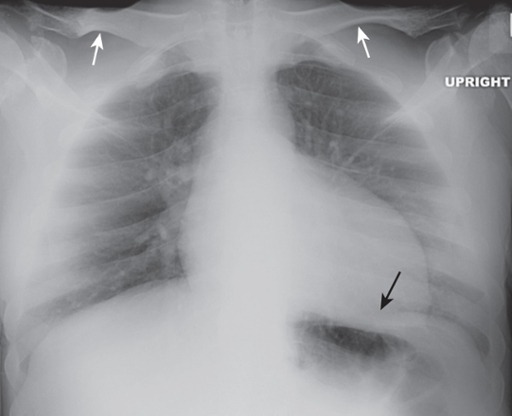

An apical lordotic view of the chest is most frequently obtained inadvertently using the portable technique in patients who are semirecumbent because they are bedridden and cannot stand. Notice how the clavicles are projected above the first ribs and their usual “S” shape is now straight (white arrows). The lordotic view also distorts the shape of the heart and produces spurious obscuration of the left hemidiaphragm (black arrow).